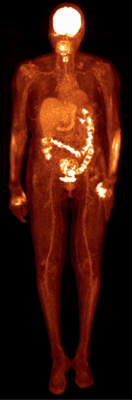

Based on Philips’ proprietary digital photon counting technology, the Vereos PET/CT is the first PET/CT system in the industry to use digital silicon photomultiplier detectors instead of traditional analog detectors, resulting in a step change in performance that approximately doubles sensitivity gain, volumetric resolution and quantitative accuracy compared to analog systems. These radical improvements can ultimately be translated into high image quality, increased diagnostic confidence, improved treatment planning and faster workflows.